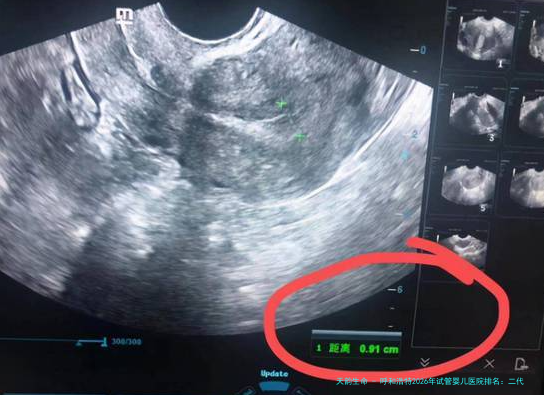

| 阴道B超监测排卵 | 1500 | 800 | 1200 | 按次计费,约需6-8次 |